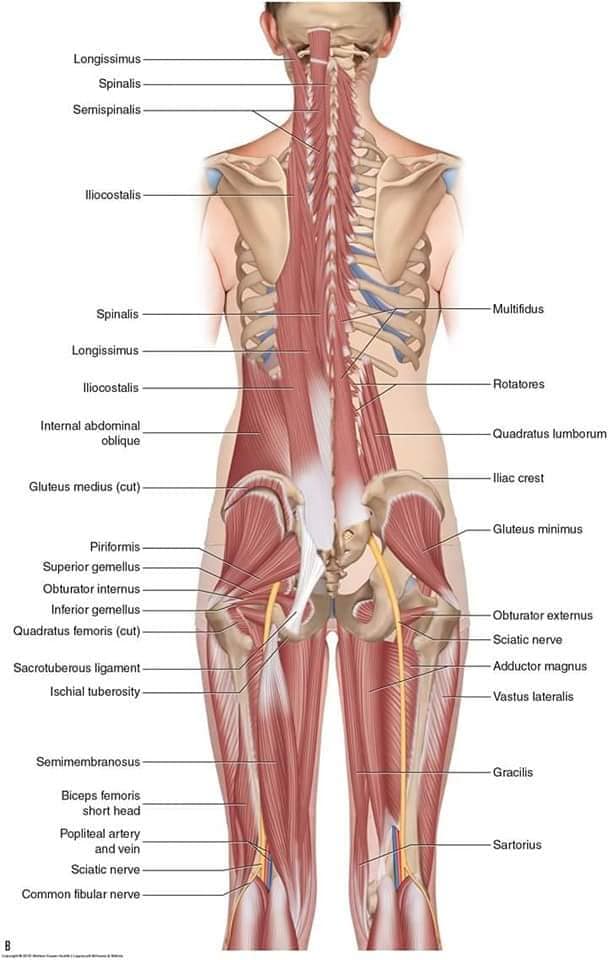

М'язова система людини є однією з основних систем організму, що відповідає за рухи, підтримання пози та стабільність. Вона складається з понад 600 м'язів, які можна класифікувати на скелетні, гладкі та серцеві м'язи. Скелетні м'язи, які є об'єктом нашого детального розгляду, дозволяють контролювати навколишній світ і виконувати різноманітні рухи. Особливу увагу в нашій статті буде приділено шейним і спинним м'язам, оскільки ці групи м'язів мають критичне значення для підтримання правильного постава та функціонування хребта.

Спинні м'язи

Спинні м'язи виконують функції підтримки хребта, а також дозволяють здійснювати рухи тулуба.

Глибинні спинні м'язи

М'язи, що забезпечують стабільність хребта: М'язи, що розташовані між хребцями: включають мускулатуру, яка забезпечує стабільність і підтримку хребта, а також дозволяє здійснювати рухи хребта.

М'язи, що здійснюють ротацію та нахили

М'язи, що забезпечують ротацію хребта: Ротаційні м'язи: допомагають у здійсненні обертальних рухів тулуба, а також у підтримці рівноваги і стабільності хребта.